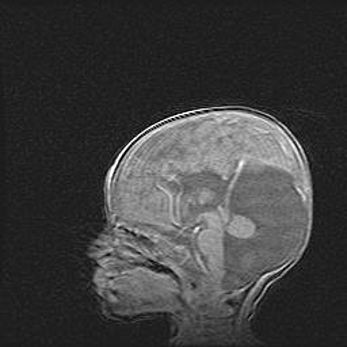

Церебральная ишемия II.

Возраст: 5 дней

Вес: 3400 г

Пол: женский

Окружность головы: 35 см

Срок гестации: 39 недель

Церебральная ишемия – это заболевание, характеризующееся недостаточностью (гипоксией) либо полным прекращением (аноксией) снабжения мозга кислородом по причине закупорки одного или нескольких сосудов. Это приводит к  что метаболическим расстройствам различной степени тяжести в тканях головного мозга, развитию коагуляционных некрозов и гибели нейронов.